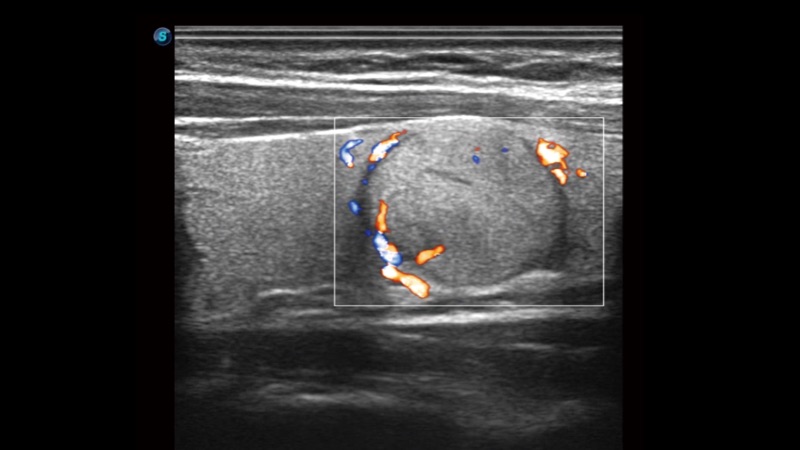

開立醫(yī)療通過不斷的技術(shù)創(chuàng)新,為大眾的生命健康提供持續(xù)關(guān)愛。P12 Plus采用全新一代超聲成像平臺(tái),新平臺(tái)旨在將真實(shí)還原組織解剖結(jié)構(gòu)作為首要目標(biāo)。平臺(tái)采用全新集成化硬件模塊,搭載新一代芯片,系統(tǒng)性能得到大幅提升,為您的診斷提供了豐富的臨床信息。優(yōu)異的圖像表現(xiàn),豐富的探頭配置,全面的應(yīng)用功能,為您日常診斷提供了可靠的助手。

彩色多普勒超聲診斷系統(tǒng)